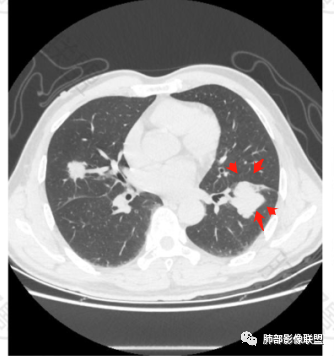

3.支气管充气征伴或不伴支气管扩张:肿瘤细胞沿肺间质及支气管黏膜下组织浸润,支气管管壁未见明显破坏,管腔内未见肿瘤细胞充填,呈现充气支气管征;充气支气管走行自然,无扭曲、僵硬,内壁管腔光滑,支气管管壁见增厚并常有管腔的扩张,含气支气管可呈串珠样不均匀扩张,扩张明显处呈空腔样或皂泡样的囊状含气影;支气管扩张目前有两种意见:一是由于肿瘤组织起源于肺间质,肿瘤沿或跨越脏器解剖结构生长,原有解剖结构残留,周围增生的纤维结缔组织牵拉导致支气管扩张;二肿瘤侵犯支气管粘膜下植物神经丛致平滑肌张力丧失;而这类支气管扩张在肿瘤治疗后有时可消失。

支气管充气征伴扩张

4.血管造影征:肿瘤组织浸润引起间质增厚、肺泡壁破坏、肺泡腔充填,而周围充盈血管走行自然,未受肿瘤侵犯。血管造影征

6.间质性改变:多位于病灶周围,可见边缘磨玻璃密度影或晕征及树芽征象,周围组织间质增厚并且有结节感,病理基础为肿瘤细胞浸润细支气管周围间质及肺泡壁。

磨玻璃影及间质小结节影